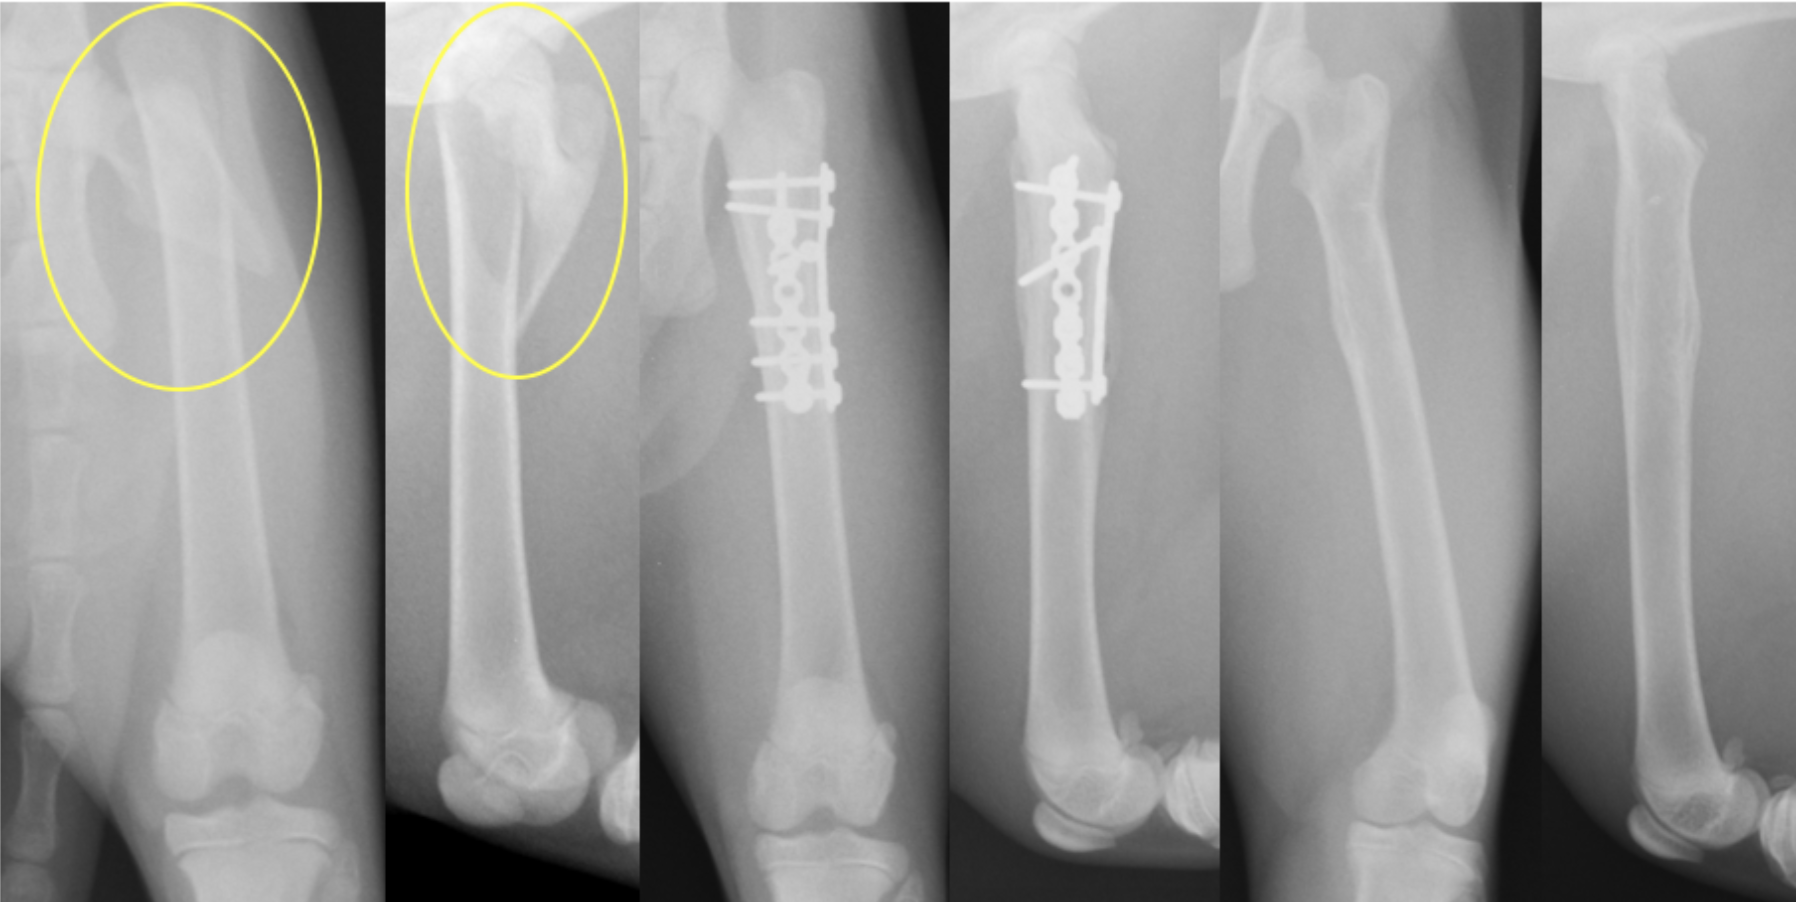

大腿骨骨折は最も癒合不全(骨の癒合が遅れる・癒合しない)が起きやすく、特に内側の骨が欠損するとインプラントの破損が起きやすいため、強固な固定・安定化が必要です。そのため、髄内ピンとプレート(プレートロッド法)やラグスクリューとプレートを合わせるような固定が理想的になります。

若齢犬の大腿骨近位の斜骨折です。斜骨折をラグスクリューである程度固定し、プレートによって支持する(守る)方法を使っています。これを中和プレートと呼ぶこともあります。